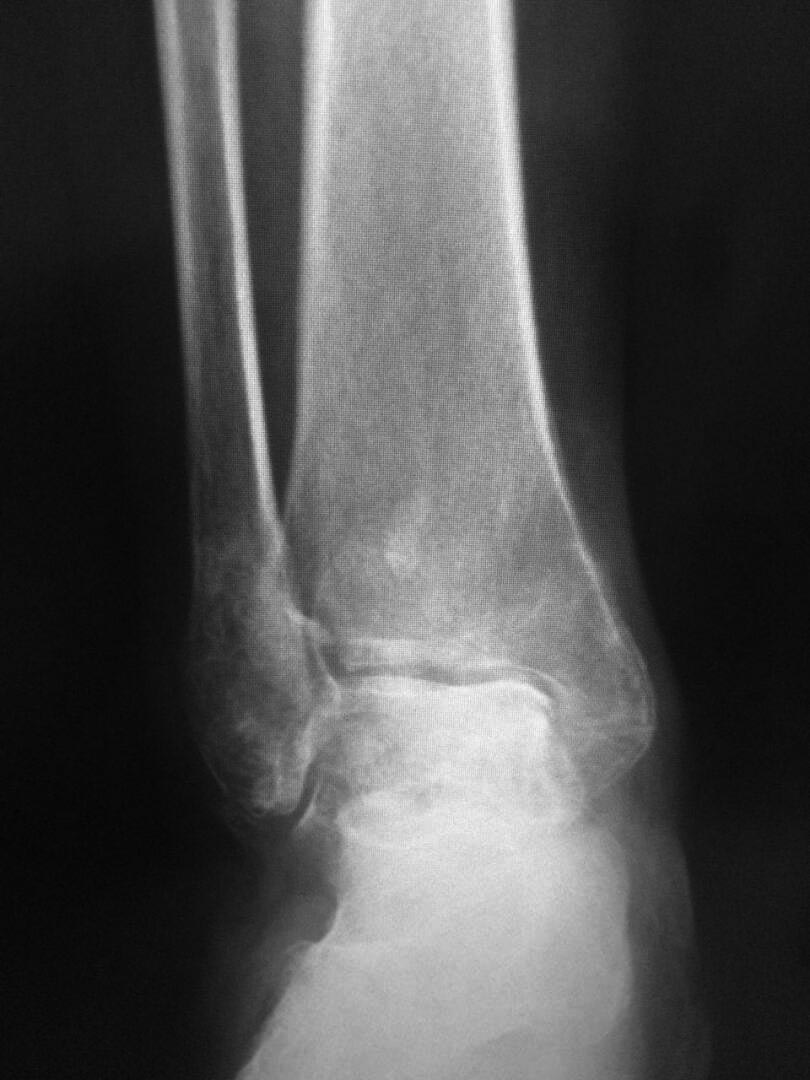

Пациентка 60л. 3 месяц назад получила травму г/стоп сустава: перелом

обеих лодыжек, заднего края с подвывыхом стопы. Нигде не лечилась. Мне

пригласили на консультацию в другую обл.  Все идет к артродезу. У нее